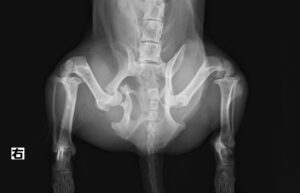

交通事故で当院夜間救急外来へ来院しました。右後肢に重度の疼痛と内出血を認め、X線検査にて複数箇所の「骨盤骨折」が見つかりました。幸い他に大きな致命傷はありませんでしたが、念の為、点滴や痛み止めを使用しながら内科治療を実施し、受傷から3日後に骨盤骨折の整復術を行いました。複雑な場所の骨折だったため、小さいプレートを駆使しながら正しい位置で固定。6週間後には元気に走り回っています。